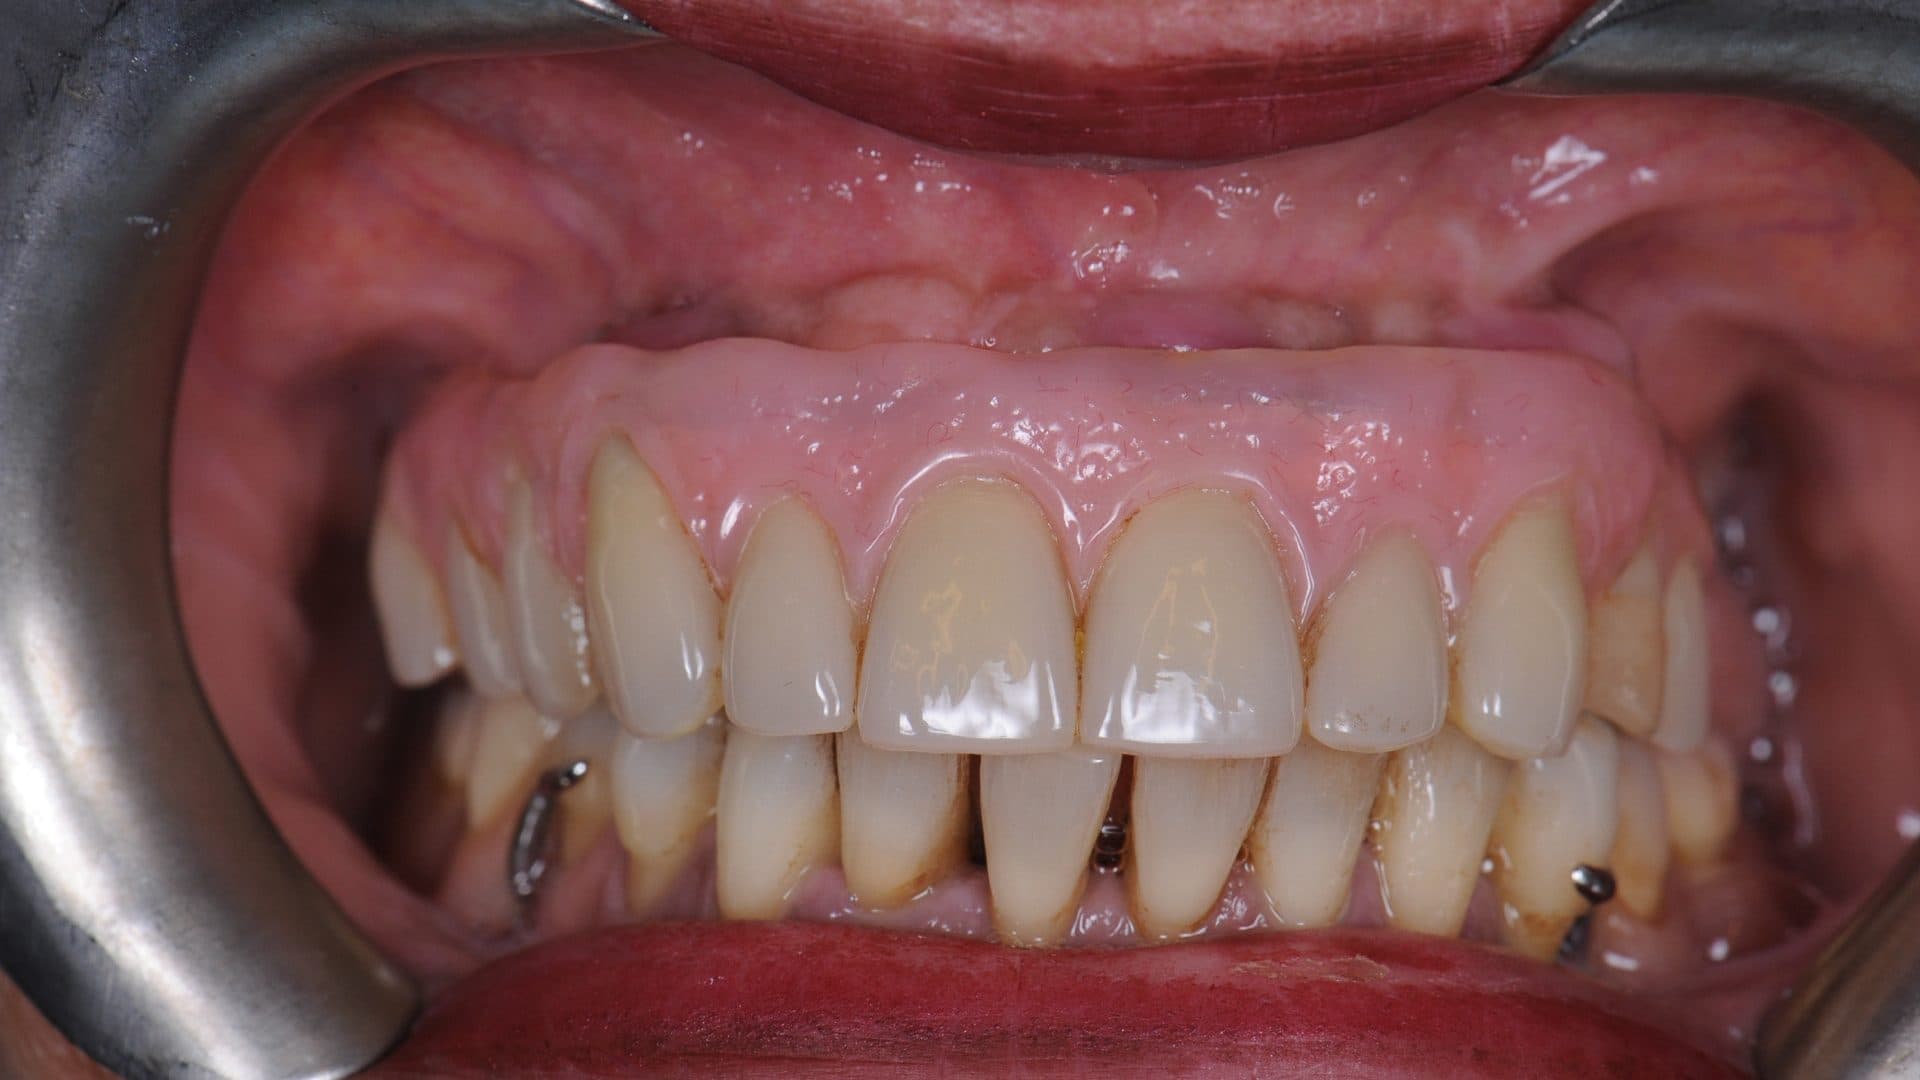

i. Even spread of the implants and flat and uniform under-surface/interface between the prosthesis and the natural gums. A deviation from this will affect the cleanability of the prosthesis, food entrapment and smell (See pictures);

Examples Of Poor Standards

ii. The access holes for the screws are located near the edges of the front teeth and in the middle of the back teeth. Any deviation from this will severly affect level of comfort, speech, and also cleanability (See pictures);